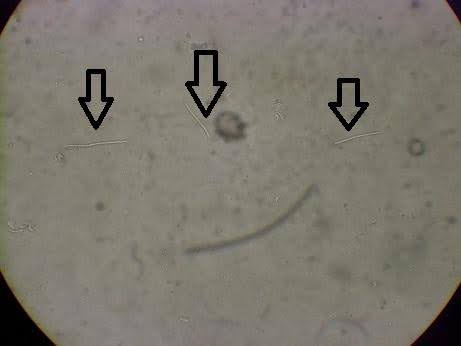

まず行ったのは糞便検査(検便)です。

顕微鏡で便を確認すると、写真で確認できるような棍棒(こんぼう)状の特徴的な菌が多数認められました。

これがいわゆるメガバクテリウム(メガバクテリア)です。

※メガバクテリウム

以前は細菌と考えられていましたが、現在は真菌(カビの仲間)に分類されています。